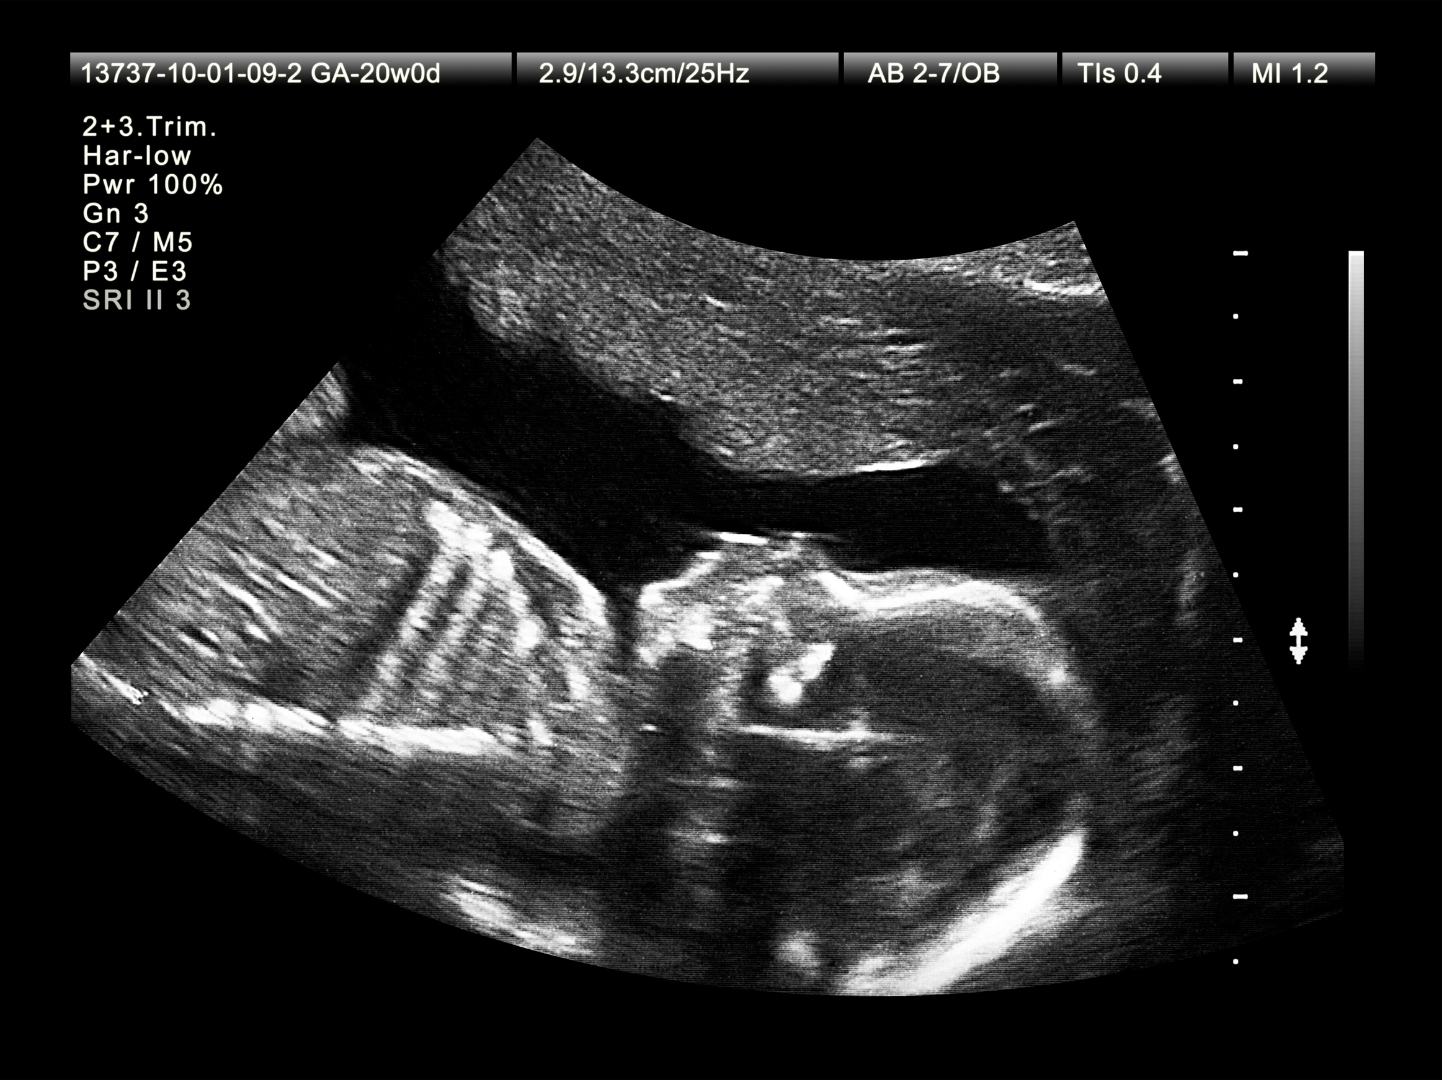

Le Canadian Medical Association Journal a récemment publié un article réclamant le changement de l'enregistrement des mortinaissances, à cause du fait que les chiffres du Canada seraient anormalement élevés par rapport à d'autres pays parce que les avortements à partir de vingt semaines sont comptés comme telles... L'article parle d'un taux de mortinatalité de plus du double d'autres pays économiquement similaires !

Ceci nous amène évidemment à nous demander s'il n'y aurait pas des bébés laissés à mourir après leur expulsion du sein maternel. Une étude conduite au Québec et publiée en 2024 avait révélé que 11,2 % des bébés avortés au 2e trimestre venaient au jour encore vivants.

L’article, intitulé « Il est temps de changer la définition et le cadre réglementaire de la mortinatalité au Canada » (Time to change Canada’s stillbirth definition and regulatory framework), explique comment le taux de mortinatalité au Canada est « artificiellement élevé » par rapport à d’autres pays parce qu’il inclut les avortements pratiqués à partir de 20 semaines dans le décompte.

« Le taux de mortinatalité au Canada est plus du double de celui des pays à revenu élevé comparables et augmente, en partie à cause des critères stricts d’enregistrement des mortinaissances », indique l’article du CMAJ.

Les critères incluent l’exigence d’« enregistrer tous les décès fœtaux avec un poids de naissance de 500 g ou plus ou un âge gestationnel de 20 semaines ou plus », ajoute l’article. « Cependant, l’inclusion dans le nombre de mortinaissances des décès fœtaux qui suivent une interruption tardive de la grossesse (à 20 à 24 semaines de gestation) est un facteur clé du statut d’exception du Canada à l’échelle internationale. »

En d’autres termes, les avortements tardifs se produisent au Canada, ils sont signalés comme des mortinaissances, et ils se produisent assez souvent pour avoir une incidence sur les statistiques nationales.